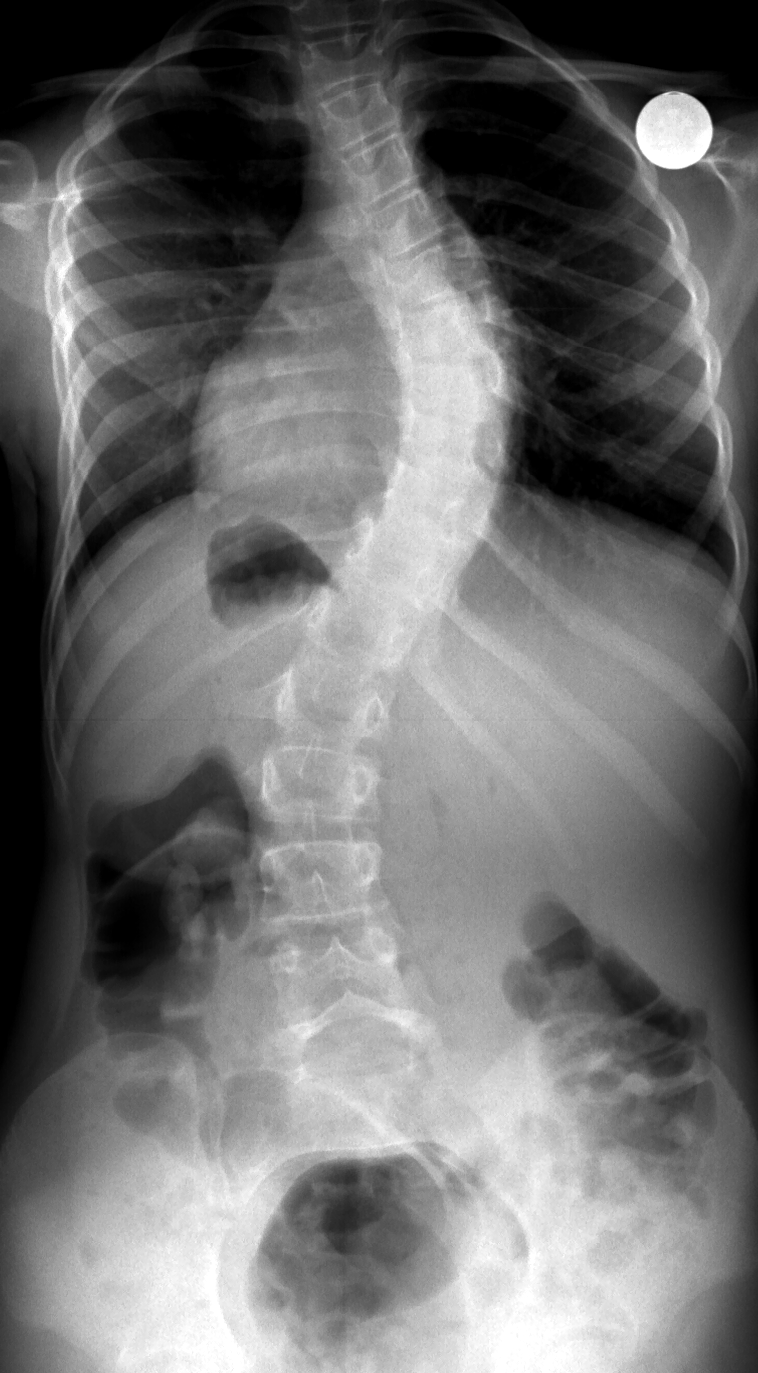

Scoliosis Xray Labeled . Include top of crest and entire. Adolescent idiopathic scoliosis is a coronal plane spinal deformity which most commonly presents in adolescent girls from ages 10 to 18. This abnormal curvature may be the result of an underlying. Adolescent idiopathic scoliosis is a structural lateral curvature of the spine evident in otherwise healthy patients between the ages of 10 and 18 years. Scoliosis is defined as a lateral spinal curvature with a cobb angle of 10° or more. As the disease progresses, the vertebrae and spinous processes in the area. Scoliosis is a complicated deformity that is characterized by both lateral curvature and vertebral rotation. Patient flat footed and bare foot. 2 view • ap erect:

Adolescent idiopathic scoliosis is a coronal plane spinal deformity which most commonly presents in adolescent girls from ages 10 to 18. Scoliosis is a complicated deformity that is characterized by both lateral curvature and vertebral rotation. Patient flat footed and bare foot. This abnormal curvature may be the result of an underlying. Adolescent idiopathic scoliosis is a structural lateral curvature of the spine evident in otherwise healthy patients between the ages of 10 and 18 years. Scoliosis is defined as a lateral spinal curvature with a cobb angle of 10° or more. 2 view • ap erect: Include top of crest and entire. As the disease progresses, the vertebrae and spinous processes in the area.